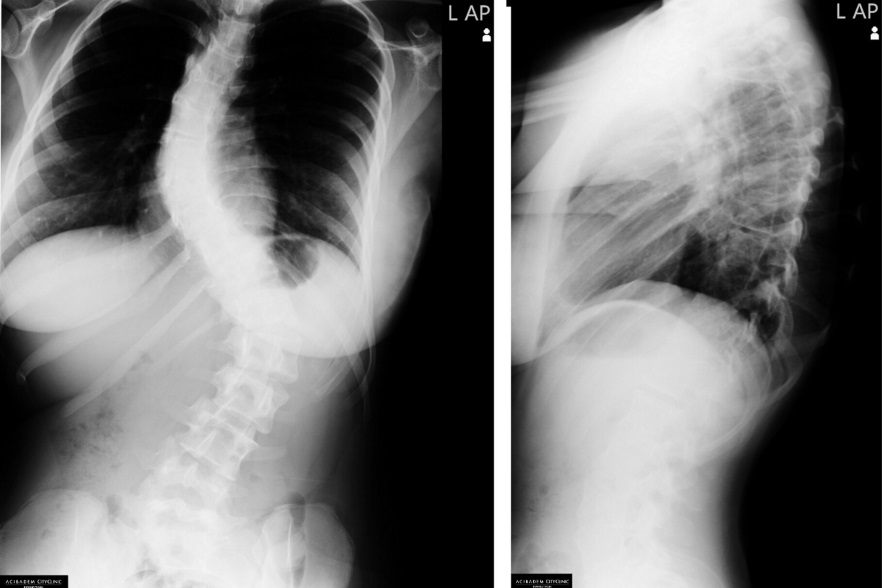

Сколиоза

Сколиозата е триизмерна деформация на гръбначния стълб, която може да се развие във всеки един момент от живота на човек - както при бебета, така и при много възрастни хора. Най-честата изява на заболяването обаче е във възрастта между 10 и 15 години.

При най-тежките случаи, прогресирали до големи градуси (над 40°), единственото лечение е хирургичното.

Оперативното лечение на деца с деформации на гръбначния стълб е крайната стъпка, която лекарите предприемат само, ако няма друг подходящ подход към заболяването!